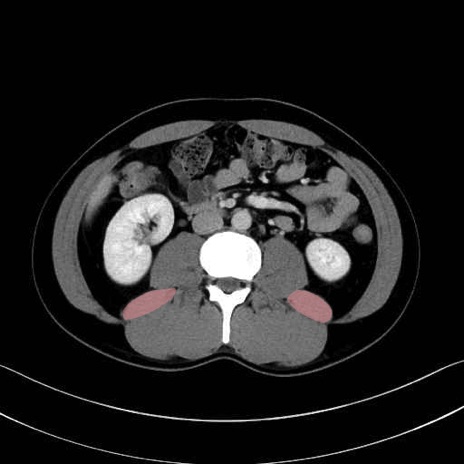

2. 腸腰筋群と骨盤底筋

大腰筋 (Psoas major)

腸骨筋 (Iliacus)